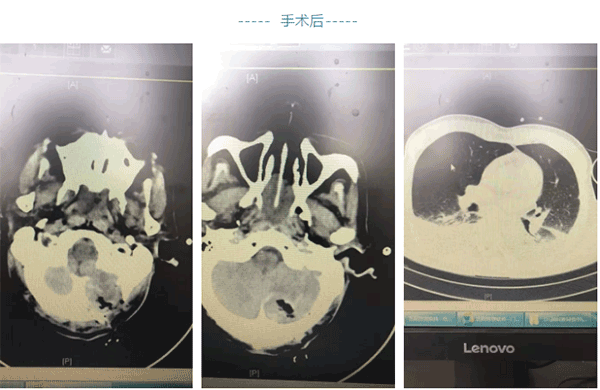

杨主任为患者输注血小板纠正血小板低下,行后颅窝开颅手术治疗,术后患者神志转清,但患者在呕吐时误吸窒息,出现呼吸衰竭、左心功能衰竭,两个脏器功能衰竭死亡率50%以上,加之患者系老年高龄,死亡率、抢救难度大大增加。转送ICU经护理的积极配合历经层层关隘,患者最终肺功能和心脏功能逐渐恢复正常。

出院前复查颅脑胸部CT示积液和肺不张胸腔积液恢复良好,患者可以正常行走,现已经顺利出院。